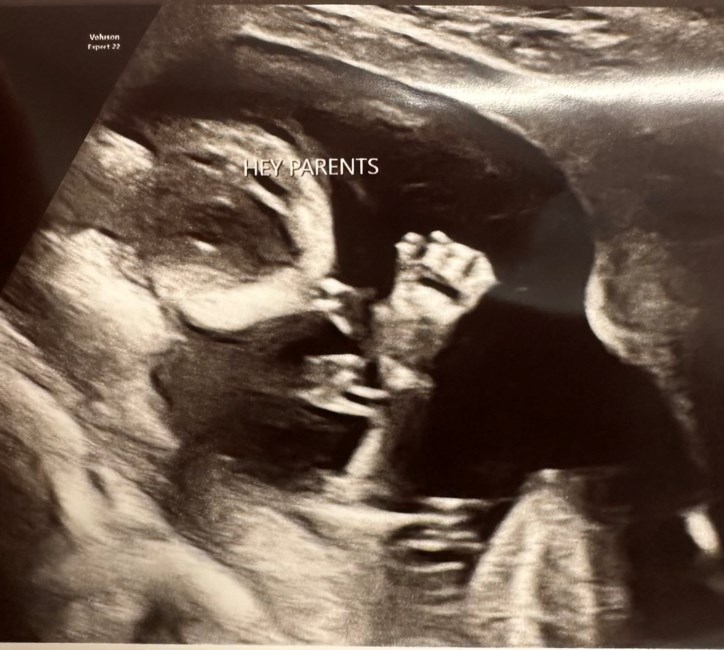

With profound sorrow and tender love, we announce the passing of our precious baby girl, Journey Janay Ross, also lovingly known to friends and family as “Berry Rose”, who was carried in love for 20 weeks and now rests in the arms of angels. Though her time with us was brief, she touched our hearts deeply and will forever remain a cherished part of our family’s story.

Though she never took a breath in this world, Journey’s presence brought immeasurable love, hope, and joy. She will forever be our little light—a reminder of the beauty, fragility, and preciousness of life.